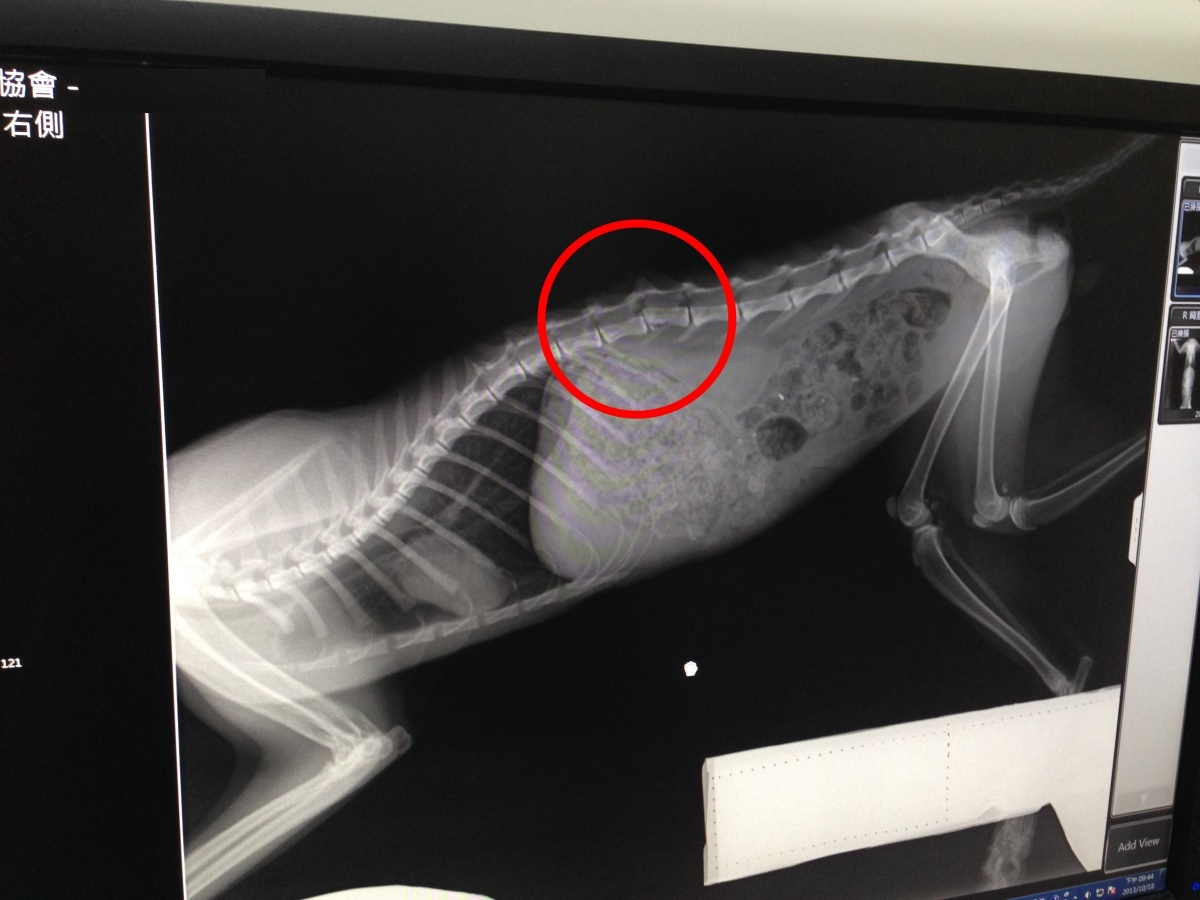

主題: 車禍貓Car被撞到後腿癱瘓,民眾通報消防隊捕抓後移送消防隊 申請者姓名: Mai Lin Lai 花色: 申請日期: 2013-11-07 09:25:51 申請者部落格: 申請者臉書網址: https://www.facebook.com/mailin.lai/media_set?set=a.686327711378991.1073741854.100000053041167&type=3 所在縣市/合作醫院: 台北市/伊甸動物醫院 治療費用: 49572元 需求人數: 52人 已結案 (2014-01-10 17:54:12) 報名人員: Jackie Kang(已付款)、邱小咪(已付款)、ADA(已付款)、大聲說 x5(已付款)、Helen Yu(已付款)、LaLa Cheng(已付款)、Sweettpg(已付款)、Yi-Jun Huang(已付款)、Freesia Tsai(已付款)、黃婷婷(已付款)、迷迷 x2(已付款)、迷迷 x2(已付款)、黃淑華(已付款)、禾惠 x2(已付款)、chdk x2(已付款)、Sek Wang、Sha C(已付款)、Eucalyptus Wu(已付款)、LittleSun(已付款)、jenny(已付款)、貓空(已付款)、張奈(已付款)、Bubu Wang(已付款)、LovelyBaby(已付款)、Akiko Tsai、Akiko Tsai(已付款)、蔡秀芳(已付款)、MILKY(已付款)、COFFEE(已付款)、Yee-Wen Lai(已付款)、柯元傑(已付款)、Mai Lin Lai(已付款)、Chen Mei Ling(已付款)、Kiki Liang(已付款)、Fidji Chen(已付款)、HuaMing Sung(已付款)、Sunny(已付款)、Olive Guan(已付款)、Woneday Wang(已付款)、洛克薩斯(已付款)、Hide、Hide(已付款)、nai(已付款)、梁咪子(已付款)、Joba Huang(已付款)、yuki x2(已付款)、 候補人員: 動物病情說明: Car是民眾通報在大樓地下室被車撞到雙腳拖行的貓,消防隊捕抓暫時安置消防隊中,本來要移交動保處,因為車禍傷勢嚴重,後腳癱瘓無法行走,所以先行救出送醫,X光檢查Car脊椎的錯位,但深層痛覺仍有反應,感覺的到疼痛,為避免大動作造成脊椎二度傷害,決定鎮定包背板固定,需要4~6周的復原時間,在醫師細心的照顧下Car越來越溫馴穩定,臨出院之際,卻開始出現鼻氣管炎的狀況,噴嚏連連,食慾也受影響,除了抗生素治療外,早晚噴霧,慢慢狀況也改善許多,因為活動受限制,Car開始出現褥瘡,現在每天需要清潔傷口,早晚幫他按摩做復健。